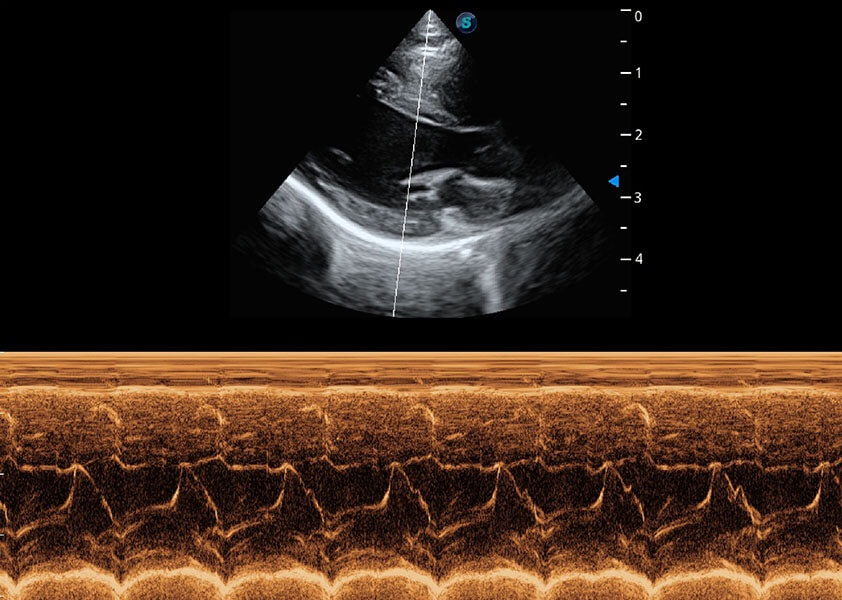

(犬)乳头肌短轴

(猫)二尖瓣M型